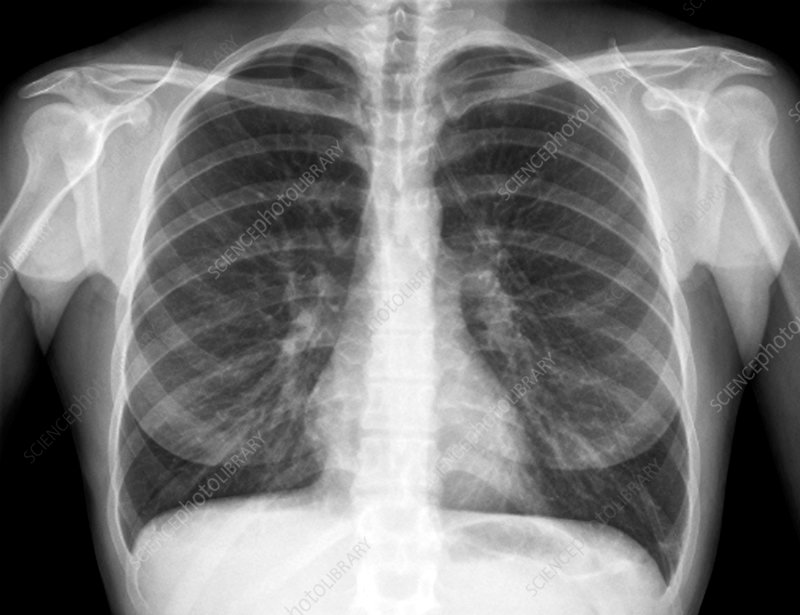

Cough, fever, cold, and body pain since yesterday

Diagnosis: Pneumonia

Certainty: Almost Certain

Author: Sadia Noreen

Date Published: Jan 23, 2025

Disease Specialty: Pulmonology

Image Type:

X Ray